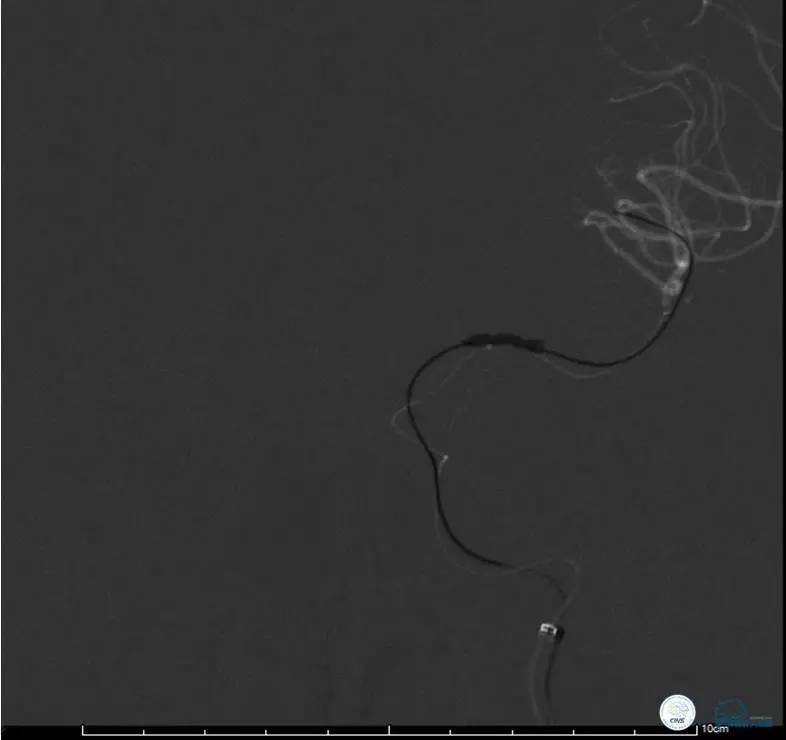

造影评价血管、判断闭塞段,微导丝小心穿过闭塞段,微导管造影,交换技术,球囊扩张,Enterprise支架。在后扩张时导丝刺破M3段血管,蛛网膜下腔出血(SAH)。

微导管进入破裂血管,栓塞弹簧圈1枚,出血停止,结束手术。继续双抗,术后2天肌力2级,神经功能恢复明显加快。

术后即刻和6天后CT,患者无明显临床症状。

半年后复查造影,无支架内再狭窄,可见弹簧圈,患者恢复至自己柱杖行走。